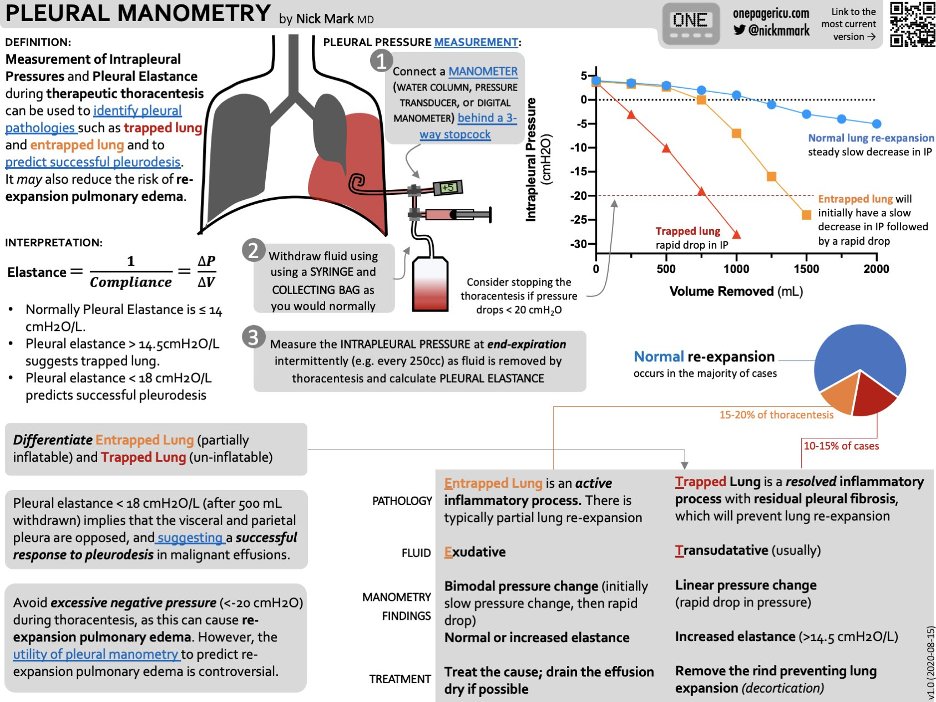

15/Another handy trick is with pleural manometry. In trapped lung you will see the pressure decrease quickly as pleural fluid is being withdrawn while in lung entrapment it will be more gradual. Check out this chart on pleural manometry by @nickmmark !